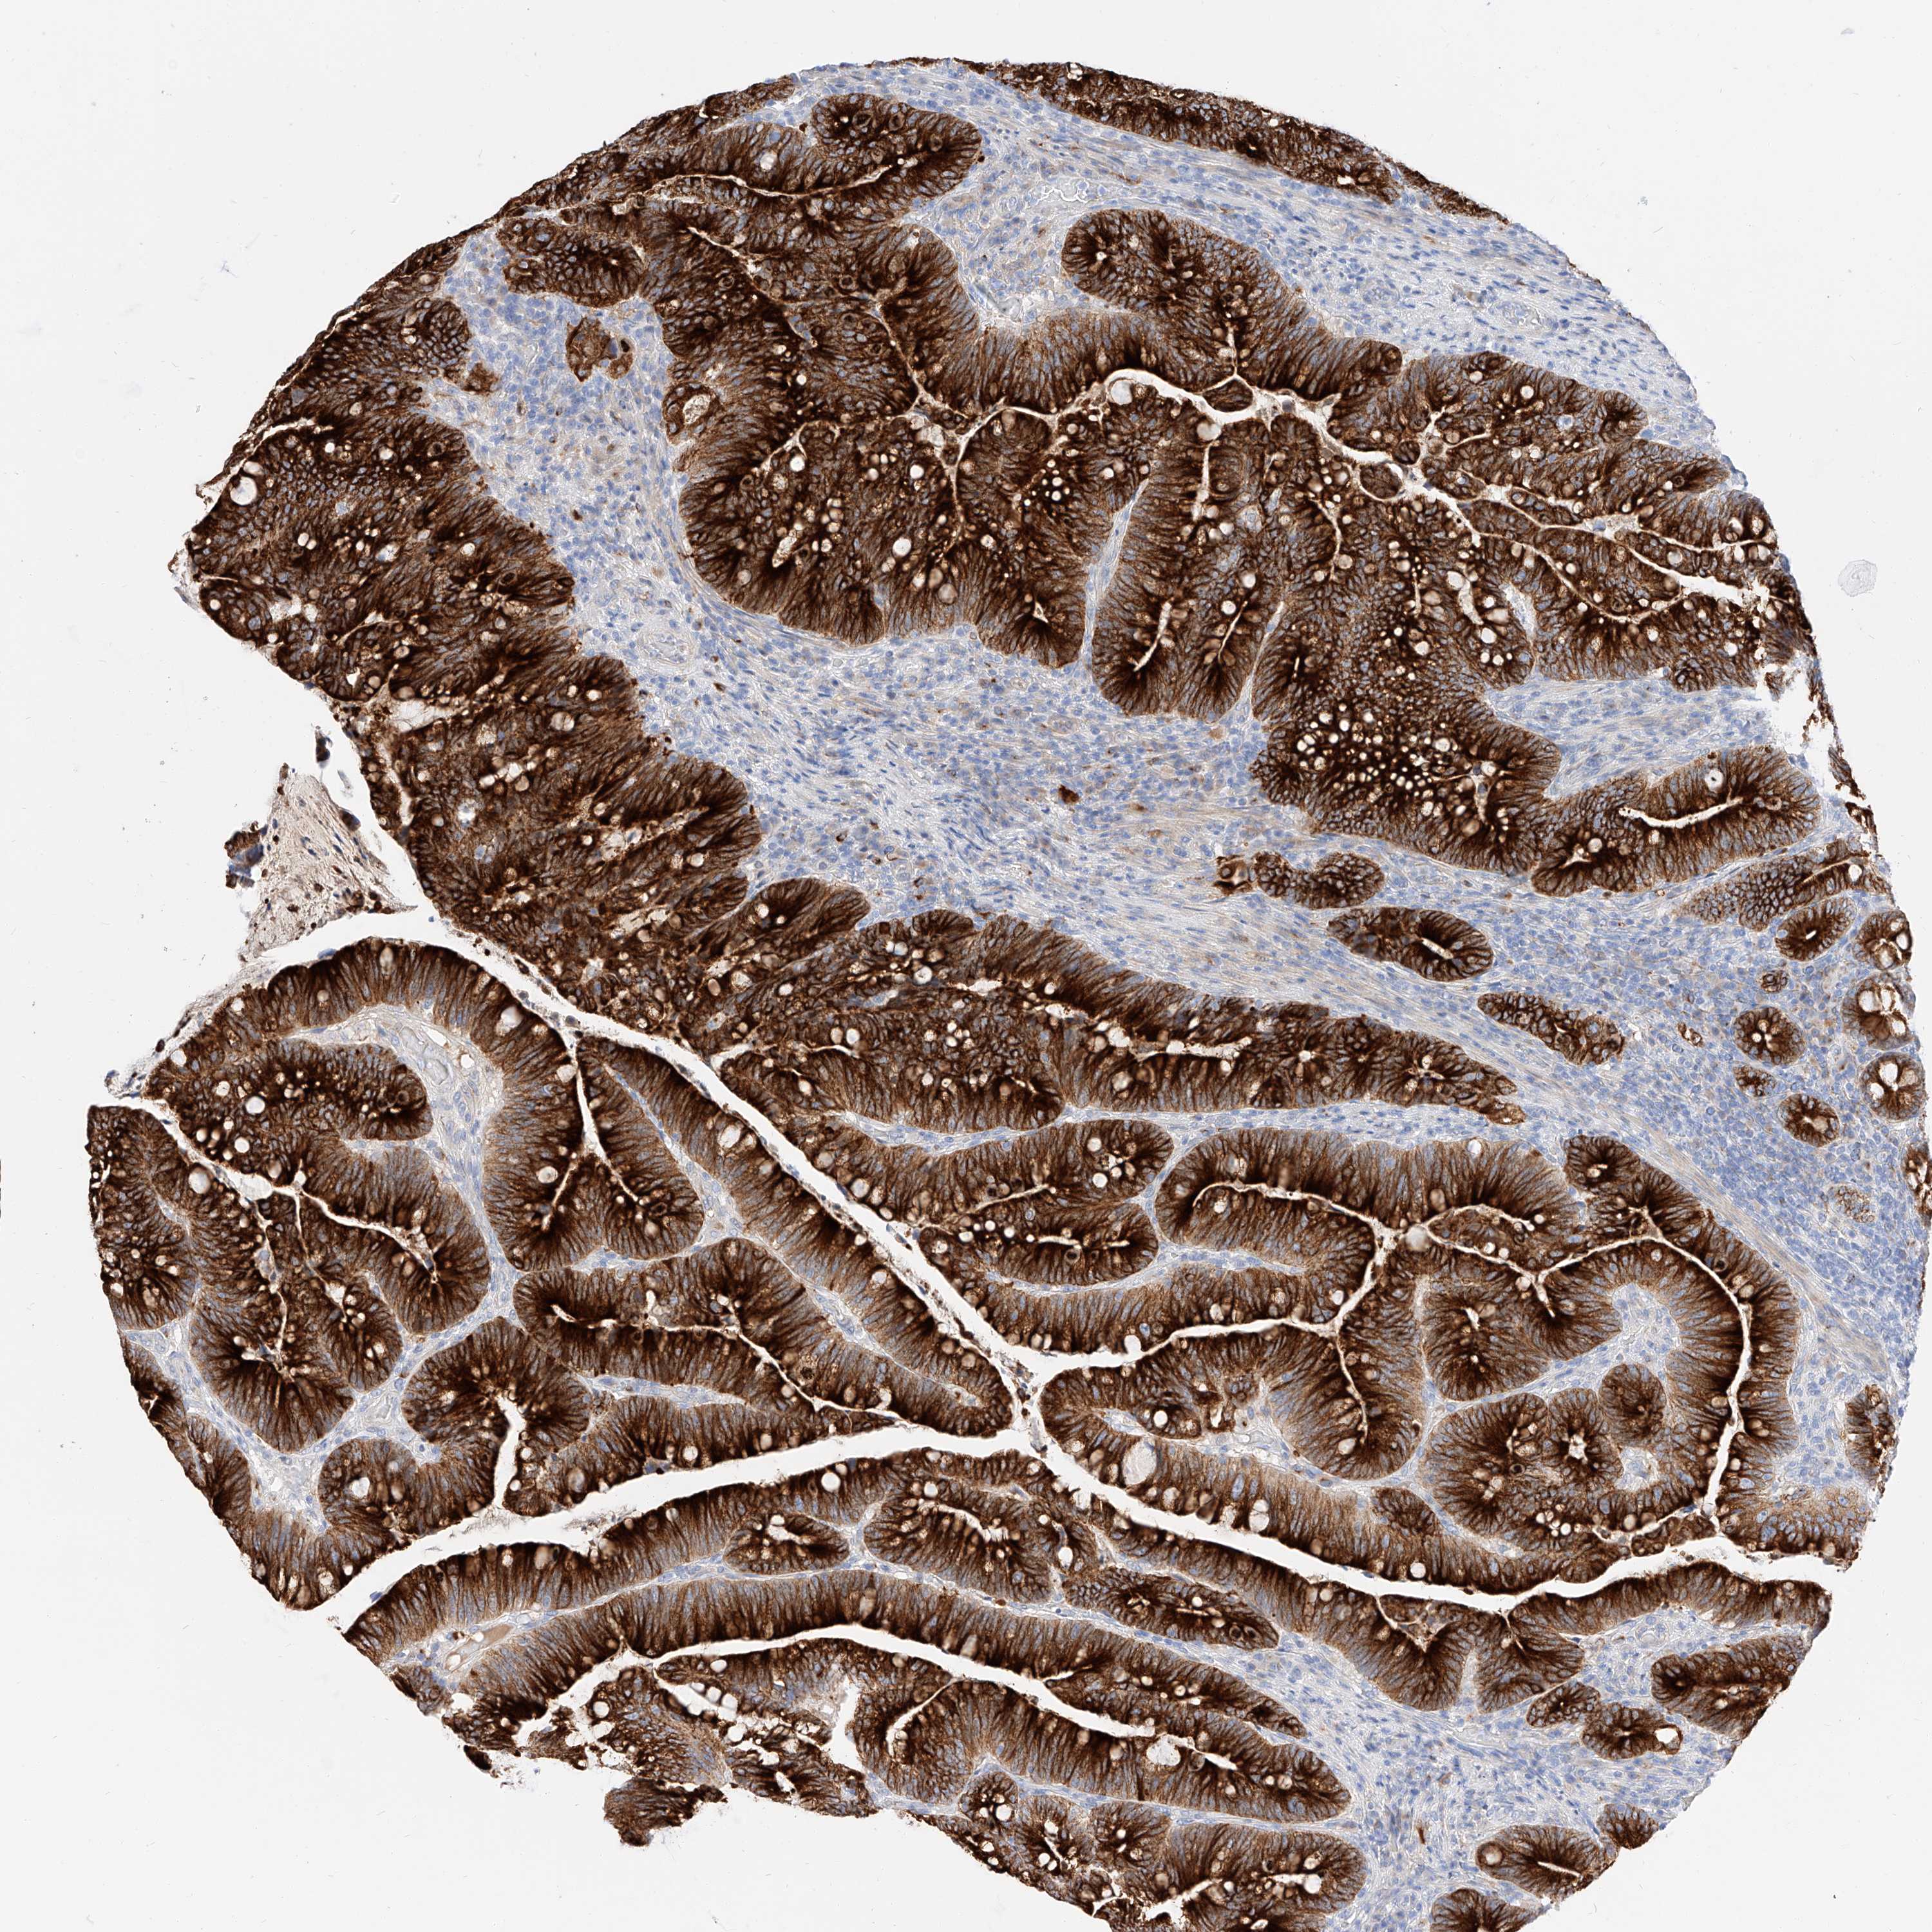

CANCER COLORECTAL CANCER Show tissue menu

COAD TCGA COAD VALIDATION READ TCGA READ VALIDATION PROTEIN COAD CPTAC PROTEIN EXPRESSION

ANTIBODIES

AND

VALIDATION